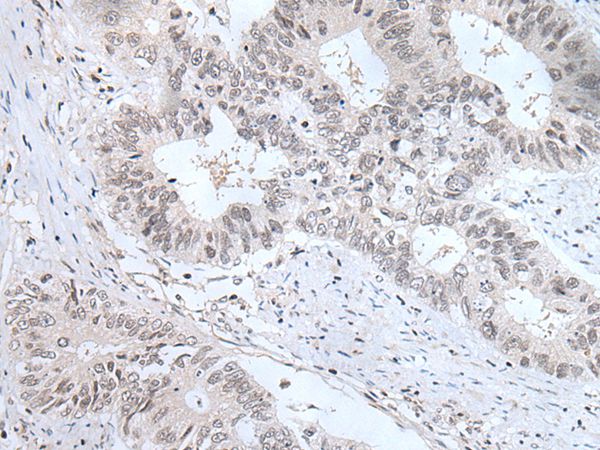

分类: 科研抗体货号: P43452别名: E2F-5应用: WB,IHC反应种属: Human,Mouse